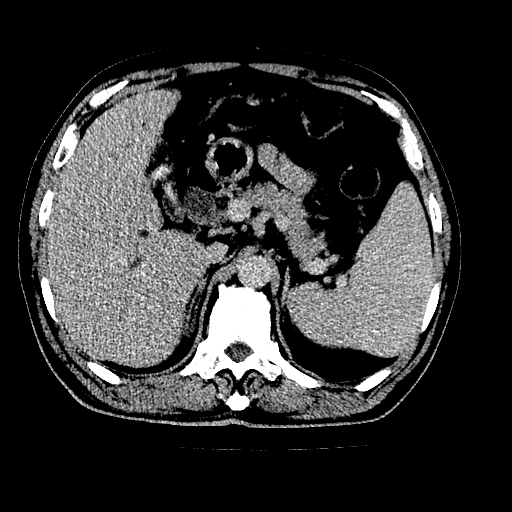

男,66岁,上腹部不适、黄染一周。彩超示:肝左叶占位,肝内胆管扩张,胆总管扩张,胆总管占位?

肝左叶不规则软组织肿块影,边缘不规整邻近肝实质受累分界不清;肝内胆管(左叶)明显扩张成“软藤状”,诊断:肝左叶胆管细胞癌。

左叶胆管细胞癌累及胆总管,门脉左支受侵,慢性胆囊炎胆结石,左肾小囊肿

肝左叶不规则软组织肿块影,边缘不规整邻近肝实质受累分界不清;肝内胆管(左叶)明显扩张成“软藤状”,诊断:肝左叶胆管细胞癌。胆囊钙乳症。

胆囊缩小,其内胆汁浓缩,也提示梗阻部位应该位于胆囊管起始部以上或是胆囊管受累及,支持肝外胆管癌。